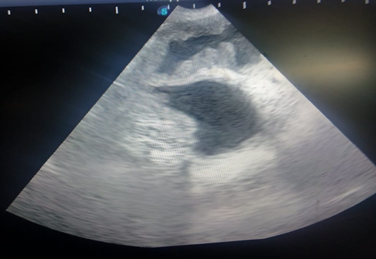

Canine pyometra is one of the most frequent reproductive organ disorders in reported in intact female dogs, particularly during the diestrus phase of estrus cycle and progesterone dominant uterus.1 Pyometra is accumulation of exudates within the uterine lumen, typically occurring during or immediately after a period of progesterone dominance. Clinical signs associated with this kind of disorder include lethargy, anorexia, polydipsia, polyuria, vomiting and unusual vaginal discharge (Kuplulu et al., 2009).2 The most accurate method of diagnosing pyometra in canines is ultrasonography.3 Both qualitative and quantitative examination is possible in diagnosing pyometra.4 In case of Pyometra, uterus will appear as distended and anechoic sacs are visualized due to pus accumulation. The advantage of ultrasonography is that it can detect the intrauterine fluid even in smaller quantity and also detect the abnormal changes in the ovaries and uterine tissue.5 Depending on the extent of uterine involvement, ultrasonographic features of pyometra may vary, the areas of uterine involvement may appear as hypoechoic or anechoic areas like if moderate involvement is there, it will appear as hypoechoic, roughly round structure ventral to ventro-lateral to the anechoic urinary bladder in transverse section. On ultrasound examination, cystic endometrial hyperplasia (CEH), which precedes pyometra, appear as small, cyst like fluid-filled regions within the endometrium (Figure 1). Similarly, transabdominal ultrasonography is effective way in diagnosing closed type of pyometra. A characteristic multiple anechoic sacculations with changes in the uterine wall thickness is visible as depicted in Figures 2–4. Therefore, ultrasound can be used as non-invasive and rapid diagnostic technique to detect the uterine pathologies like CEH and pyometra.6–10

Figure 3 Ultrasonographic view of uterus showing corrugations of uterine wall suggestive of CEH and anechoic to hypoechoic contents in the lumen.